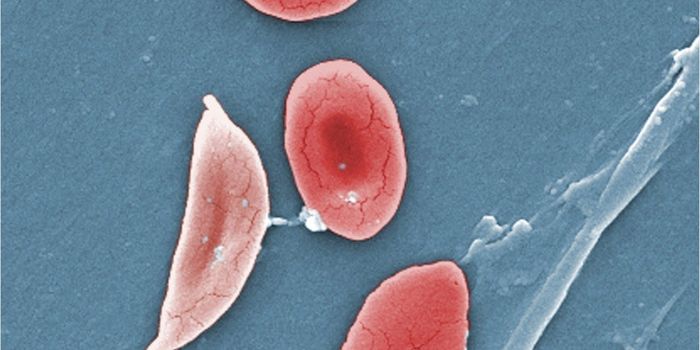

MAY 05, 2016VideosCancer spreads by the process of metastasis, where malignant cells break off from tumors in one part of the body and tra ...